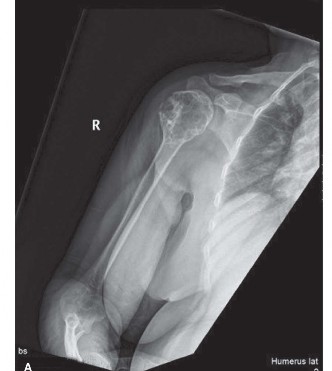

The clinical presentation detailed above concludes with the necessity to rule out impending pathological fracture. The MRI demonstrated a T1 hypointense, T2 hyperintense lobulated lesion with a distinct hypointense rim. Minimal perilesional edema was noted, and there was no soft tissue mass or cortical breakthrough. Contrast enhancement was peripheral and septal, lacking the solid, aggressive, and diffuse enhancement pattern typically associated with metastatic adenocarcinoma. However, given the patient's advanced age and oncologic history, a definitive tissue diagnosis was mandatory to differentiate between an atypical presentation of a benign entity, such as an adult Non-Ossifying Fibroma (NOF) or Benign Fibrous Histiocytoma, and a solitary lytic metastasis.

The diagnostic evaluation of a solitary lytic bone lesion in an older adult with a known history of malignancy represents a significant clinical challenge in orthopedic oncology. Statistically, a destructive bone lesion in a patient over the age of 40 with a history of carcinoma must be considered metastatic until proven otherwise. Prostate carcinoma is one of the most common primary malignancies to metastasize to bone, alongside breast, lung, renal, and thyroid carcinomas. While prostate metastases are classically osteoblastic, resulting in sclerotic lesions, mixed lytic-blastic or purely osteolytic variants can occur, particularly in advanced or heavily treated disease.

Conversely, Non-Ossifying Fibromas are benign, self-limiting developmental defects of bone primarily seen in the pediatric and adolescent populations. They are estimated to occur in up to 30-40% of all children, typically arising in the metaphyses of long bones, most frequently the distal femur and proximal tibia. The natural history of an NOF involves gradual migration away from the physis into the diaphysis, followed by progressive ossification and resolution by skeletal maturity. The persistence of an NOF into the seventh decade of life is exceedingly rare. When such histologically identical lesions are symptomatic in adults, they are often reclassified as Benign Fibrous Histiocytomas.

Standard orthogonal radiographs of the entire femur must be reviewed to assess for synchronous lesions and to determine the appropriate length of the implant. Advanced imaging is mandatory. A computed tomography (CT) scan provides superior detail regarding cortical integrity, the exact dimensions of the defect, and the presence of occult microfractures. Magnetic Resonance Imaging (MRI) is essential for delineating the intramedullary extent of the tumor, identifying any soft tissue extension, and visualizing the proximity of the lesion to the neurovascular bundle. Systemic staging, including a CT of the chest, abdomen, and pelvis, alongside a whole-body bone scintigraphy or PET-CT, is required to rule out disseminated disease, which would shift the treatment paradigm strictly toward palliation.